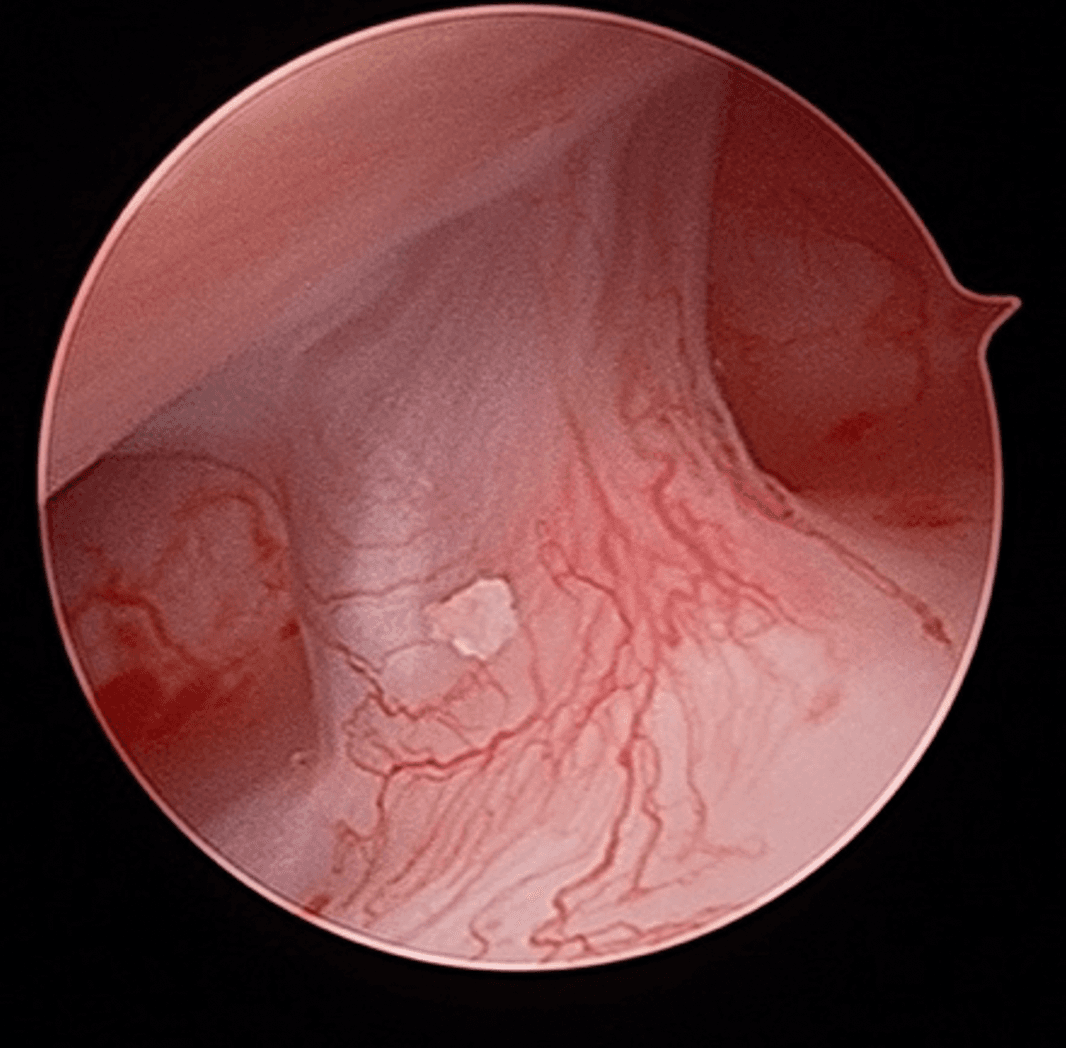

Certains DTM par contre nécessiteront une approche chirurgicale en raison de leur nature ou de l’impact significatif qu’ils ont sur la fonction. En règle générale, le chirurgien tend à choisir l’approche minimalement invasive qui est la plus appropriée dans les circonstances. Cela peut impliquer une simple infiltration articulaire, une chirurgie sous caméra (arthroscopie; approche qui permet d’avoir accès et manipuler le contenu articulaire sans avoir à ouvrir) ou dans certains cas une chirurgie ouverte (arthrotomie). Les Drs Poirier et Badri détiennent notamment des expertises dans ces champs de pratiques de par leur expérience et leur surspécialisation.

Chirurgie sous arthroscopie